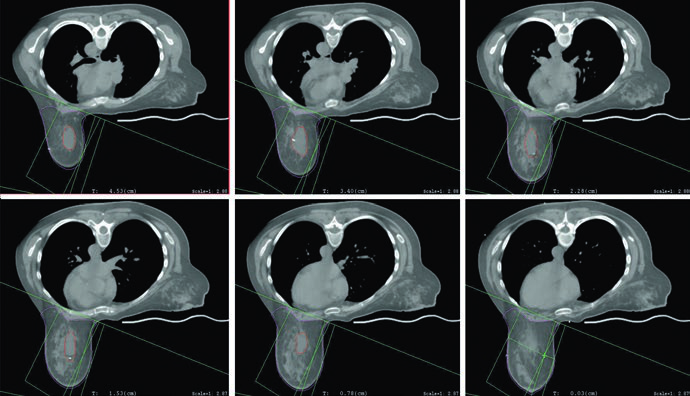

Boost do leito tumoral e uso seletivo de APBI

O capítulo é claro ao resumir o papel do boost. Irradiar o leito tumoral após a mama inteira reduz ainda mais o risco de recorrência local, mas esse reforço pode ser omitido em pacientes de baixo risco. O texto não transforma essa decisão em fórmula rígida. Ele só define o ponto de partida: boost tem valor reconhecido, porém existe um grupo em que a omissão pode ser aceitável.

Quando o boost é indicado, o planejamento mais comum descrito pelos autores usa elétrons em incidência en face. A seleção da energia deve obedecer à profundidade do leito tumoral somada a uma margem, sem ultrapassar a superfície anterior dos músculos peitorais. A figura do boost em posição supina torna isso quase didático ao mostrar a escolha de 12 MeV para garantir cobertura da isodose de 90% até a superfície anterior do peitoral. Se o leito é profundo, o texto admite uma alternativa prática: considerar mini-tangentes.

A APBI aparece em seguida, com formulação cuidadosa. Ainda não é apresentada como padrão de tratamento, mas já é considerada alternativa aceitável para pacientes selecionadas de baixo risco e com doença unifocal. O capítulo não vai além disso, e essa contenção ajuda. Em vez de prometer uma mudança de paradigma, ele delimita um território específico em que a irradiação parcial acelerada pode ser usada de forma responsável.

As figuras e a tabela explicam como esse volume é construído. A cavidade de lumpectomia deve incorporar seroma, clipes e alterações marcantes do tecido glandular. A tabela recomenda expansão de 1,0 a 1,5 cm para o CTV e de 0,5 a 1,0 cm para o PTV, conforme incerteza de setup e movimento previsto. Já a legenda da figura de APBI mostra um exemplo típico: CTV de 1,5 cm ao redor da cavidade, excluindo músculo peitoral, costela e parede torácica, sem ultrapassar o tecido mamário contornado e sem chegar à pele, ficando restrito a 5 mm da superfície. Em seguida, o PTV é formado por expansão de aproximadamente 5 mm em torno do CTV, dependendo da incerteza institucional.

Essa combinação entre tabela e figura afasta dois erros comuns. O primeiro é expandir o volume de forma automática, sem checar onde o tecido mamário realmente termina. O segundo é transformar o PTV em um volume anatomicamente limpo demais, esquecendo que o próprio capítulo permite que ele ultrapasse a superfície e avance para peitoral ou parede torácica quando isso decorre da margem de setup. Em APBI, o texto pede duas coisas ao mesmo tempo: disciplina anatômica no CTV e honestidade geométrica no PTV.

A figura do plano de APBI fecha esse bloco de forma coerente com o restante do capítulo. O arranjo usa mini-tangentes fotônicos combinados com um campo de elétrons en face. Não há nenhuma tentativa de tratar APBI como algo descolado do raciocínio da mama inteira. O que muda é o volume abordado, mas o capítulo continua exigindo o mesmo cuidado com orientação dos campos, profundidade útil do boost e correspondência entre anatomia operada e distribuição de dose.